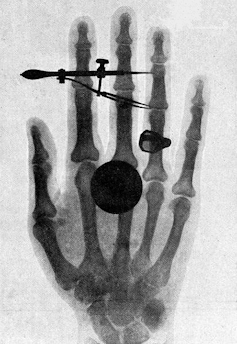

What began as hand drawings has morphed over the past 150 years with the help of new technologies. The advent of sophisticated imaging techniques such as X-rays in 1895, electron microscopes in 1931, 3D modeling in the 1960s and magnetic resonance imaging, or MRI in 1973 made it easier for scientists to share what they were seeing in the lab. In fact, Wilhelm Roentgen, a physics professor who first discovered the X-ray, made the first human X-ray image with his wife’s hand.